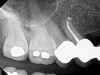

Fig 2. Tooth No. 14 was treated with silver points. In Figure 2, tooth No. 18 with mesial canals treated with Sargenti paste. The hallmark radiographic appearance of this technique is the light radiopacity within the canal system, as in Figure 3.

Figure 2